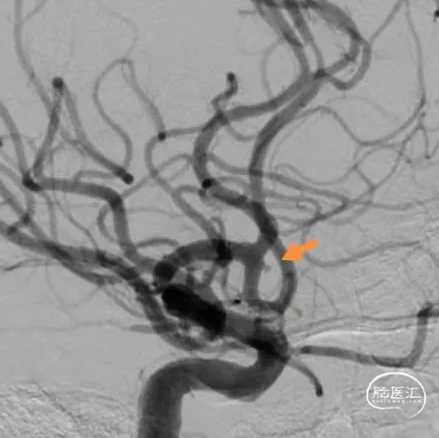

术前影像

栓塞过程

填塞第一枚Jasper®SS弹簧圈顺利;由于瘤囊较小,担心弹簧圈的稳定性,选择支架半释放后,顺利填入第2枚Jasper®SS弹簧圈。造影显示动脉瘤致密填塞,随后完全释放支架。

术后即刻影像